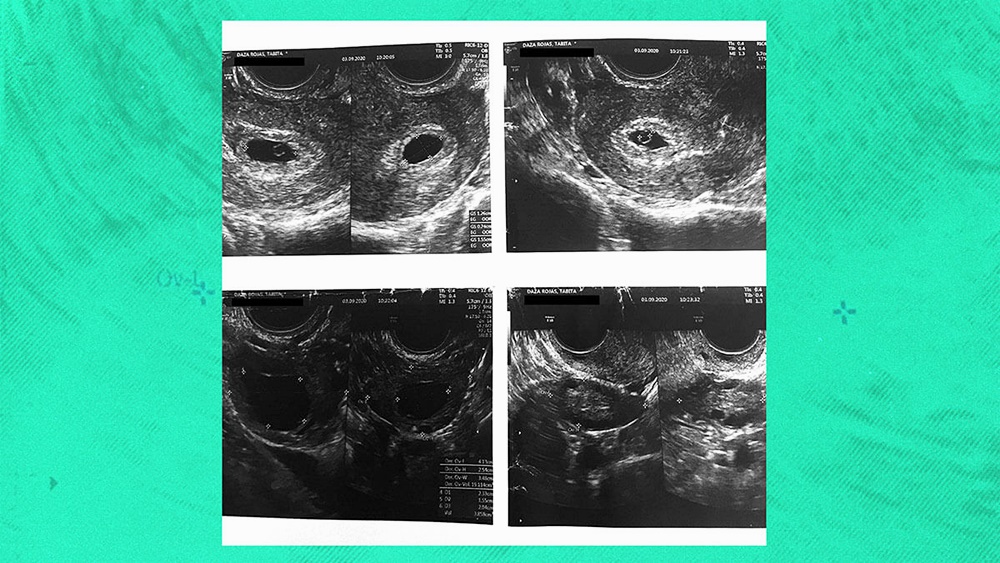

현재 칠레에서는 약 170명의 여성들이 원치 않는 임신으로 고통받고 있습니다. 이들은 낙태도 할 수 없는 상황인데요. 바로 성폭행을 당해 임신을 했거나 태아나 임신부의 생명이 위험한 경우에만 낙태가 허용되기 때문입니다. 과연 이들은 왜 임신을 하게 된 것일까요? 보건소에서 무상으로 제공한 피임약 때문이었습니다.

그러나 이 사이 불량 피임약으로 인해 임신한 여성들이 속속들이 나오기 시작했습니다. 원치 않게 임신을 하게 된 한 여성은 자신이 복용한 피임약이 회수 대상이었다는 사실을 뒤늦게 확인했는데요. 이후 보건센터를 찾아가 낙태 시술을 해달라고 요구했습니다. 그러나 보건센터에서는 이런 경우는 낙태 사유가 아니라며 이 여성의 낙태 요구를 거부했죠. 이 여성은 소송을 제기하기도 했는데요. 재판부에서는 이 여성의 주장을 받아들여 보건센터에게 '낙태를 긍정적으로 검토하라'라고 명령하기도 했습니다.